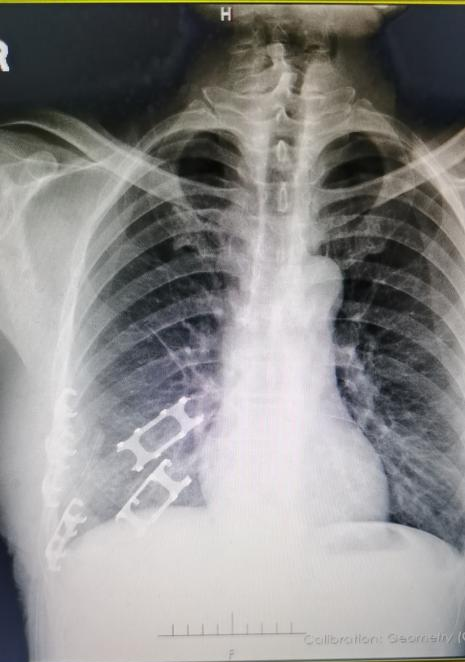

患者男,55岁,因“车祸致胸部复合伤右侧多发性肋骨骨折,胸腔积液,肺部挫伤”入院。我院胸外科主任医师韩锋带领其团队,在麻醉科的积极配合下,采用TiNi记忆合金环抱式接骨器对患者顺利进行了“肋骨骨折切开复位内固定术”,帮助患者解除病痛。患者术后3天拔除胸腔引流管,术后5天临床好转出院,治疗效果较好。

术前影像

术后影像